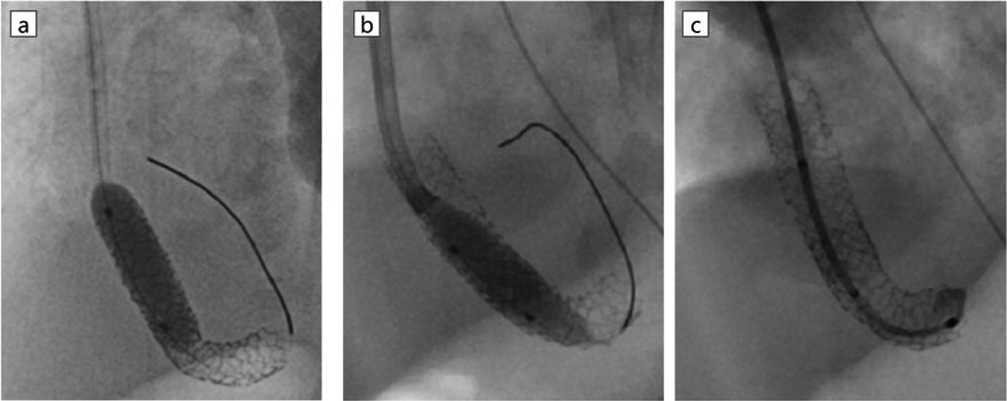

Fig. 1 Chest X-ray

Chest X-ray shows severe pulmonary congestion and scoliosis.

入院時,心拍数156回/分,血圧66/23 mmHg,呼吸回数46回/分で経皮的酸素飽和度86%(経鼻的持続陽圧呼吸療法PEEP 5 mmHg,FiO2 0.21),胸部聴診で肺雑音なし,心音整,心雑音は聴取しなかった.胸部X線で心胸郭比57%,両側肺血管陰影の増強を認めた(Fig. 1).血液検査で特記すべき異常なし.心臓超音波検査では右房,右室の拡大を認め,左室拡張末期径10.3 mm(正常期待値の76%),左室駆出率68%,心房中隔欠損4.9 mm,圧較差なく右左短絡,左右肺静脈が合流して共通肺静脈腔を形成し,共通肺静脈腔から垂直静脈が左門脈へ還流していた.垂直静脈(vertical vein: VV)は横隔膜を貫通する部位では狭窄なく,垂直静脈の左門脈合流部から静脈管(ductus venosus: DV)にかけてU字型に走行しており(Fig. 2a),同部位で狭窄があり,PVOを認めた(Fig. 2b).血流波形は連続性であり,最大流速1.6 m/s,平均圧較差7 mmHgであった.動脈管は両方向短絡だった.心外疾患として,椎体・右胸郭形成不全,右内反足・右膝拘縮,右腎低形成と診断された.遺伝染色体疾患の精査のため,術後に遺伝染色体科へのコンサルトを行い,染色体検査が行われたが正常核型であり,VACTERL連合と診断された.